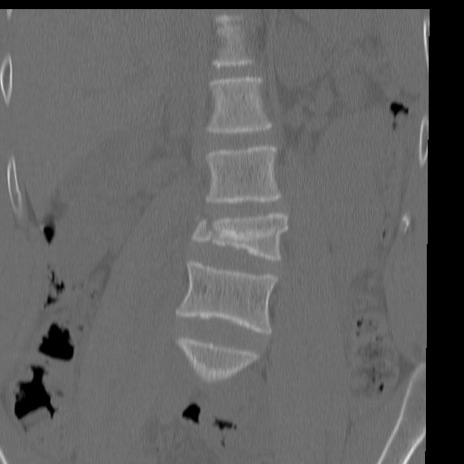

症例3 腰椎CT(冠状断像)

【症例】30歳代男性

【主訴】腰痛

【現病歴】本日旅行先で観光中に、友人と衝突し転倒し受傷。

【身体所見】麻痺なし、右下腿内側前面外側、左下腿内側に知覚鈍麻・しびれ

異常所見と診断は?

腰椎CT